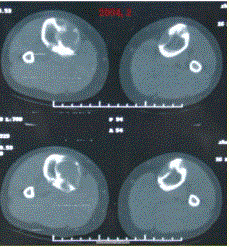

问题 患者女,20岁,右小腿疼痛1周。行双小腿正侧位CR,并行双小腿CT及MR扫描,见下图。 对于此病变的征象,描述不正确的是

选项 A.双侧胫骨骨干不规则膨胀性溶骨破坏 B.病灶边缘清楚,可见硬化缘 C.病灶呈磨砂玻璃样密度 D.在T1WI与T2WI上均表现为低信号,提示为纤维组织 E.病灶内可见多发囊状长T1,长T2信号影,为液化坏死区,提示病变为恶性病变

答案 E